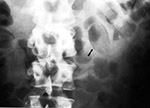

Ingested drug packets |

Radiographs of adults who were smuggling drugs. A packet is visible in the transverse colon (arrow in a). Relatively dense packets are visible in the transverse and descending colons in b and c. (Courtesy Charles A. Rohrmann, Jr., M.D., University of Washington, Seattle). From Hunter, 1994 |